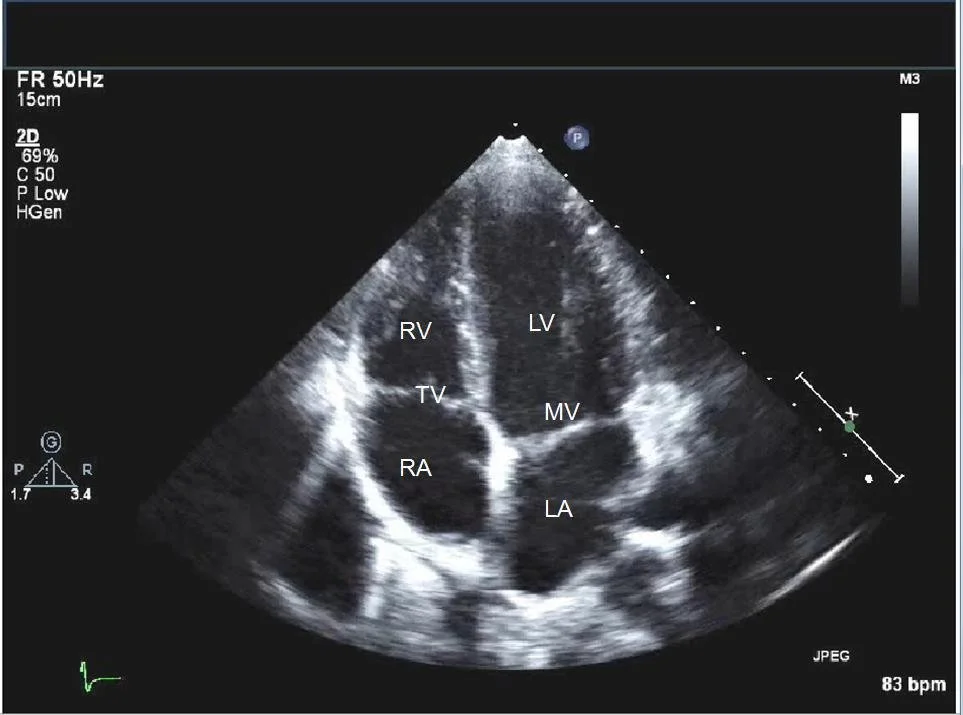

Investigations and diagnosis of breathlessness.

Echocardiography and NTproBNP blood tests to aid heart failure diagnosis. Access to cardiac MRI in Dundee for causes of heart failure.

Dr Szwejkowski’s current practice involves all aspects of general cardiology, heart failure, pacemaker device implantation and follow up, heart rhythm management and cardiac investigations including transoesophageal echocardiography, heart monitoring, loop recorder implantation and echocardiography interpretation.